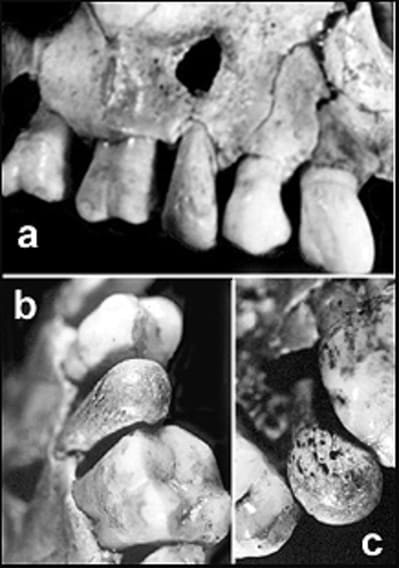

Ça appartient à une momie , d'après les facettes d'usures , c'est un homme , 1mètre 52 , d'une famille aisée , très aisée même . Il avait 2 enfants , et un jardin bien irrigué , probablement les jardins de Baby Love , Babylone pardon .

> A mon avis , c'est une phalange .

la corticale est trop mince plutot un os plus gros

je suis l'avis de alapex, on dirait bien une 3eme phallange...

une phalange de quoi, être humain, animal?

La grande usure des faces occlusales me feraient plus pencher pour un étrusque.

...qui aurait fait du tourisme dentaire , et c'est retrouvé avec une vertèbre terminale de la queue d'un chat en guise d'implant ...

pas égyptien, pas de momies non plus